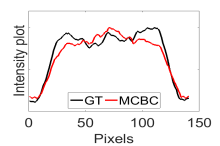

The calculated correlation coefficient (), SNR, as well as CNR values for all tested methods in the synthetic phantom experiment are shown in Table II. As seen in Table II, the proposed NCBC method achieved the highest , CNR as well as SNR values when compared to that of other tested methods. Visual results from the bias-corrected DW-MR synthetic phantom data produced using different tested methods is shown in Fig. 2(c-i). It can be observed that the MCBC, LEMS, and proposed NCBC method were able to achieve the best level of bias correction when compared to the other tested methods. This is particularly apparent in the peripheral zone (PZ) of the prostate gland as highlighted using red ROIs in Fig. 2(a-i), where intensity inhomogeneities are still present to a significant degree in the bias-corrected phantom data produced using the LS, SCIC, SGD and BCFCM methods, while strong inhomogeneity correction performance is achieved using MCBC, LEMS, and the proposed NCBC method. Furthermore, it can be observed that NCBC exhibited minimal intensity inhomogeneities when compared with MCBC and LEMS, particularly in the area that is highlighted using Red ROIs. To better represent the outperforming of proposed NCBC method in terms of bias correction using synthetic phantom, the data intensity profiles corresponding to the drawn blue line in Fig. 3(a) are shown in Fig. 3(b) for uncorrected data (red color plot) versus ground truth data (black color plot) and in Fig. 3(c-i) for corrected data using different tested methods (red color plots) versus ground truth data (black color plots). As the intensity profiles of Fig. 3(b-i) show, NCBC method was resulted in an intensity profile with the most flatness and less amount of variation compared to the intensity profiles of uncorrected image as well as reconstructed images using other tested methods as such confirms the better performance of proposed NCBC method in terms of bias field correction.